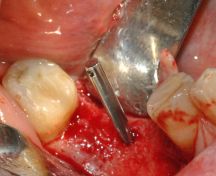

Preparazione del sito implantare con ultrasuoni, si previene l'insorgenza di deiscenze e fenestrazioni tipiche del twist drill da 3.5mm in creste con moderato riassorbimento orizzontale

Piezosurgery: preparazione del sito implantare in 46

PREPARAZIONE DIFFERENZIALE DELLA CORTICALE LINGUALE CON INSERTO DIAMANTATO OT4

PREVENZIONE DELLA DEISCENZA VESTIBOLARE